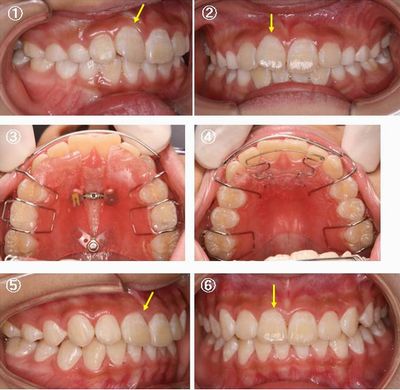

8歳4カ月の女の子の症例です。右上前歯のゆがみ(写真①②)が気になるそうです。

スペース不足のために前歯が斜めになってしまいました。下の前歯も少しかたつきがあります。

まず、ファンタイプの床拡大装置(写真③)を使ってスペース不足を改善しました。第二乳臼歯が抜けた後、閉鎖型床矯正装置(写真④)に交換しました。装置を交換して約2カ月で前歯4本がきれいなU字型になりました。上の前歯がきれいに並んだため、下の前歯も自然にきれいに並びました(写真⑤⑥)。